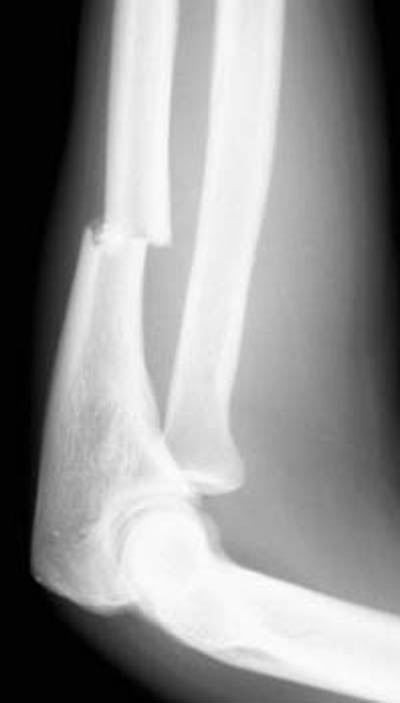

11) What abnormalities of the elbow can be observed in the image below?

12) Based on your findings, what fracture is shown in the above image?